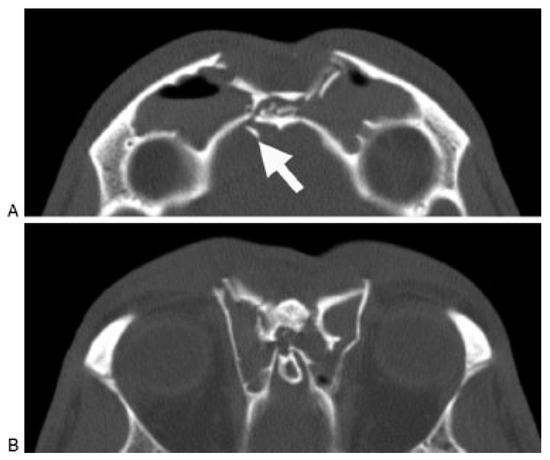

A thin-cut (1.0 to 1.5 mm) axial, coronal, and sagittal computed tomography (CT) scan is the radiological gold standard for diagnosis of frontal sinus fractures. Axial images provide the best information about the anterior and posterior tables (Figure 2); coronal images are used to assess the sinus floor and orbital roof (Figure 3). Sagittal reconstructions can be useful in assessing the patency of the frontal recess (Figure 4), and three-dimensional recon- structions may help to visualize the external contour deformity seen less clearly with two-dimensional cuts alone (Figure 5).

Figure 2.

Axial computed tomography scan demonstrating a frontal sinus fracture involving both the anterior and poster- ior tables. (A) Marked anterior table disruption. The white arrow points out a displaced posterior table bone fragment. (B) Disruption of the nasofrontal recess.